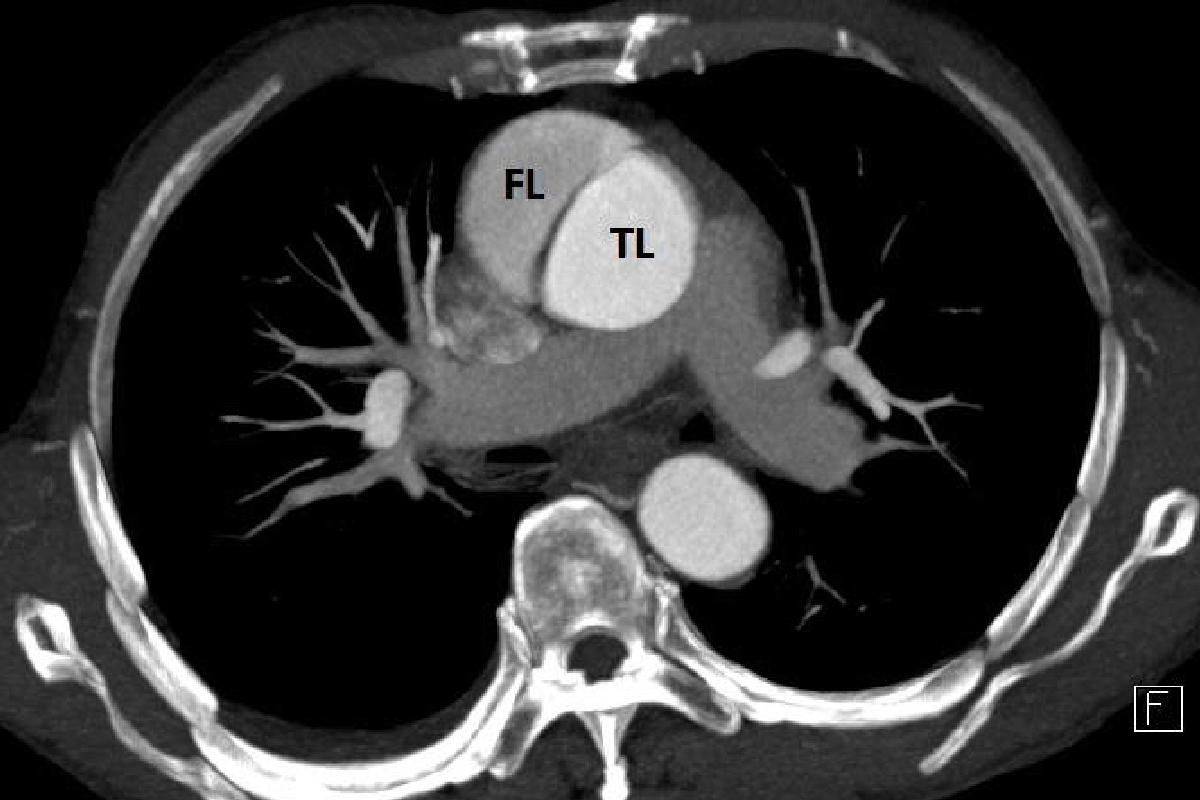

A 47-year-old non-diabetic, hypertensive male patient was admitted with sudden onset chest pain, severe headache, pain, and weakness of both limbs for 2-3 hrs at Sir Ganga Ram Hospital. He was unable to move his lower limbs. Peripheral pulses were absent in the right upper limb and both lower limbs. Echo showed moderate aortic valve leak with a dissection flap in ascending aorta. CT Aortogram confirmed Type A aortic dissection from the level of the heart valve up to the division of aorta into arteries of lower extremities. In view of the diagnosis, he was shifted to OT for emergency surgery.